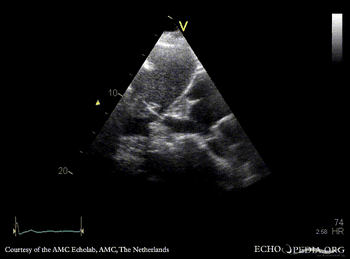

Obstruction of vena cava inferior

Subcostal view: obstruction of vena cava inferior from outside the heart Subcostal view with Color Doppler: high velocity flow in vena cava inferior